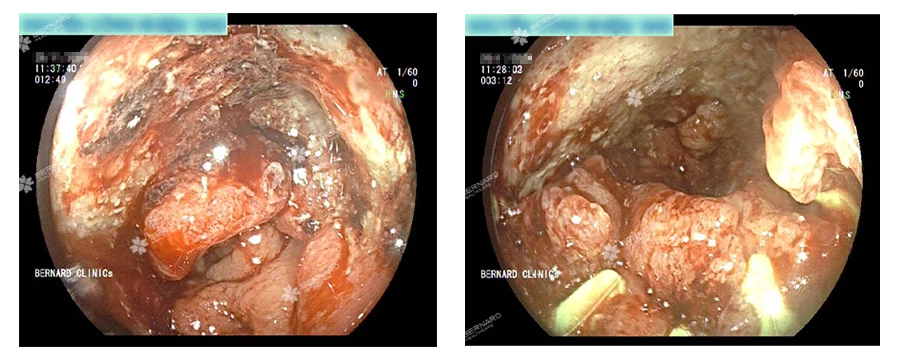

Kết quả nội soi phát hiện: Tại đoạn trực tràng cách hậu môn khoảng 14–18cm có một tổn thương u sùi, nhiễm cứng.

Mẫu sinh thiết lấy ngay trong lúc nội soi nhanh chóng được gửi đi giải phẫu bệnh. Kết quả ghi nhận hình ảnh tân sản tế bào tuyến, nhân dị dạng ái kiềm, tỉ lệ N/C > 1, các tế bào xếp thành tuyến không điển hình, xác nhận tổn thương tại trực tràng là ung thư, dạng Carcinoma tuyến biệt hóa trung bình.